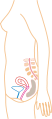

Traditionally, doctors have measured pregnancy from a number of convenient points, including the day of last menstruation, ovulation, fertilization, implantation and chemical detection. In medicine, pregnancy is often defined as beginning when the developing embryo becomes implanted into the endometrial lining of a woman's uterus. In some cases where complications may have arisen, the fertilized egg might implant itself in the fallopian tubes or the cervix, causing an ectopic pregnancy. Most pregnant women do not have any specific signs or symptoms of implantation, although it is not uncommon to experience light bleeding at implantation. Some women will also experience cramping during their first trimester. This is usually of no concern unless there is spotting or bleeding as well. The outer layers of the embryo grow and form a placenta, for the purpose of receiving essential nutrients through the uterine wall, or endometrium. The umbilical cord in a newborn child consists of the remnants of the connection to the placenta. The developing embryo undergoes tremendous growth and changes during the process of foetal development.

The body must change its physiological and homeostatic mechanisms in pregnancy to ensure the fetus is provided for. Increases in blood sugar, breathing and cardiac output are all required.

Cardiovascular changes

Blood volume increases by 40% in the first two trimesters. This is due to an increase in plasma volume through increased aldosterone. Progesterone may also interact with the aldosterone receptor, thus leading to increased levels. Red blood cell numbers increase due to increased erythropoietin levels.

Cardiac function is also modified, with increase heart rate and increased stroke volume. A decrease in vagal tone and increase in sympathetic tone is the cause. Blood volume increases act to increase stroke volume of the heart via Starling's law. After pregnancy the change in stroke volume is not reversed. Cardiac output rises from 4 to 7 litres in the 2nd trimester

Blood pressure also fluctuates. In the first trimester it falls. Initially this is due to decreased sensitivity to angiotensin and vasodilation provoked by increased blood volume. Later however, it is caused by decreased resistance to the growing uteroplacental bed.

Respiratory changes

Decreased functional residual capacity is seen, typically falling from 1.7 to 1.35 litres, due to the compression of the diaphragm by the uterus. Tidal volume increases, from 0.45 to 0.65 litres, giving an increase in pulmonary ventilation. This is necessary to meet the increased oxygen requirement of the body, which reaches 50ml/min - 20ml of which goes to reproductive tissues.

Renal changes